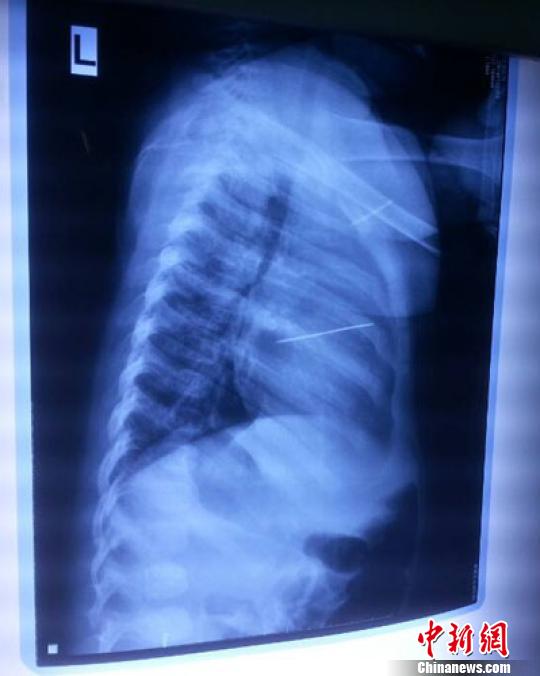

女嬰胸片提示心臟里面扎了一個(gè)縫衣針 蔡迅翔 攝

醫(yī)院胸心外科主任翟波介紹說,1月22日,小患者彤彤因?yàn)榘l(fā)燒抽搐來醫(yī)院就診,常規(guī)檢查時(shí)發(fā)現(xiàn)孩子心臟里面扎了一個(gè)縫衣針。

“第二天上午,我們做了個(gè)緊急彩超檢查,發(fā)現(xiàn)針是從患者右心室表面刺入,穿破室間隔,到達(dá)左心房,中間還有一部分損害到二尖瓣。于23號下午,我們就做了一個(gè)緊急手術(shù),手術(shù)中發(fā)現(xiàn),這枚針已經(jīng)刺入心臟,沒入了右心室的下面,表面已經(jīng)看不到針了,僅能看到一個(gè)小針眼,還在往外滲血,一點(diǎn)一點(diǎn)的滲,心包腔里面大概有100多毫升的出血,心包上一個(gè)洞,針在右心室表面刺入以后,穿過室間隔,在二尖瓣的上方,進(jìn)入了左心房,在針的四周,有很多纖維沉積物,包繞著這枚針?!钡圆ㄕf,他們把針取出來以后,測量了一下,長度大概是五厘米,同時(shí)發(fā)現(xiàn)這個(gè)針給患者左心房的后壁造成了一定的損傷,左心房的后壁已經(jīng)損傷了三分之二,還剩下有左心房的外膜,很薄的一層,如果這一層再破的話,這個(gè)孩子將會引起大出血,很快就會死亡。